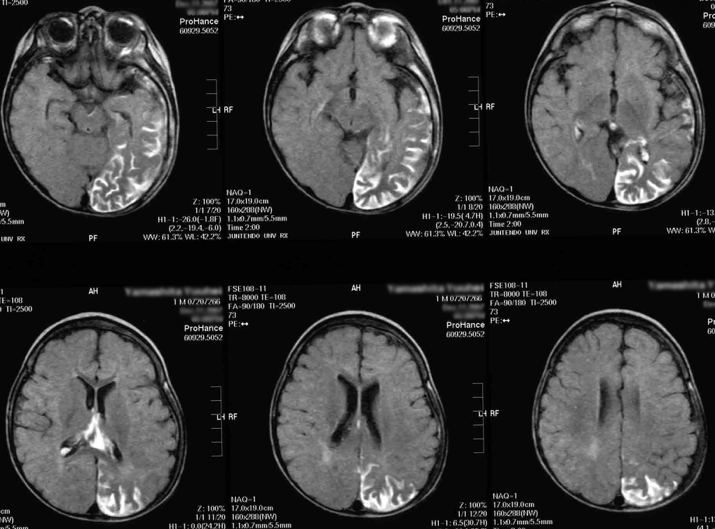

お子様の医師がSWSの可能性を疑う場合、CTやMRIスキャンなどの画像検査を指示します。これらの検査では脳の詳細な画像が得られるため、医師は脳損傷の兆候を見つけることができます。